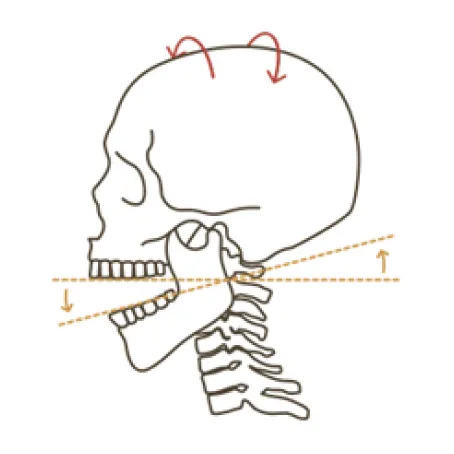

턱관절 교정의 핵심?

두개골과 경추를 함께 교정하는 것!

두개골 + 턱관절 + 상부 경추 (목뼈 1, 2번) 교정이 중요합니다.

우리 몸 중 움직임이 가장 많은 턱관절은 상부 경추 (목뼈 1,2번)를 중심축으로 움직입니다.

이 상부 경추가 틀어지면 후두골을 제대로 받치지 못하고, 두개골 또한 점점 틀어져 안면비대칭이 나타나게 됩니다.

턱관절 이상 (뇌로 올라가는 신경과 혈관이 꼬인 상태)이 있으면 목뼈 1번, 2번과 두개골에 이상 (중추신경계 기능저하)을 초래하며 전신의 구조와 기능에 이상을 일으켜 전신질환을 일으킵니다.